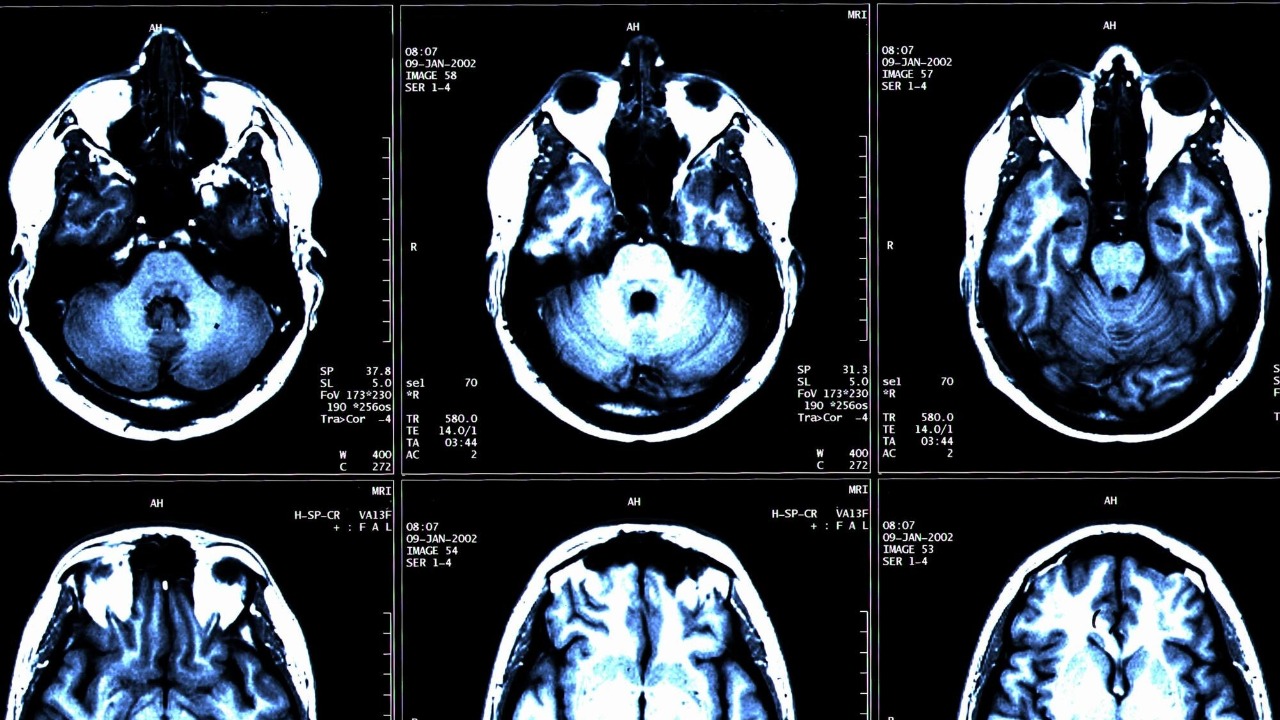

Dementia is a general term for a decline in mental ability severe enough to interfere with daily life. It’s not a specific disease, but a broad category encompassing a range of conditions, including Alzheimer’s disease and vascular dementia. These conditions affect memory, thinking, and social abilities to a degree that hinders a person’s ability to function independently.

According to the World Health Organization, around 50 million people worldwide have dementia, and nearly 10 million new cases emerge each year. This number is expected to triple by 2050, making dementia one of the most significant health crises of our time. Beyond the devastating emotional impact on patients and their families, dementia also carries a substantial financial burden, with the global cost estimated to be around $1 trillion annually.